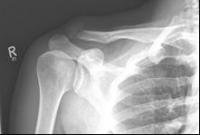

Schlüsselbein 4        Schlüsselbein 5

Pictures: Here, an angle-stable plate was used to supply the clavicle fracture near the shoulder joint. This plate makes it possible to anchor many screws in the fragment and thus obtain a good stabilization.